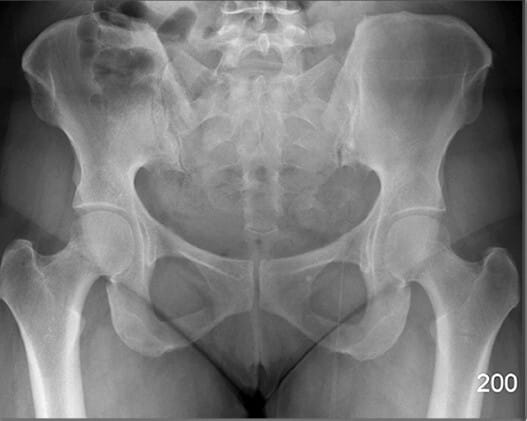

FEMUR

대퇴골두 (Head of Femur)

| 대퇴골두 (Head of Femur) |

| ✅ 비구에 삽입되어 고관절을 이루는 구형 구조물로, AP view에서 관절 중심부의 둥근 음영으로 나타납니다. |

| 🔴 대퇴골두의 위치와 관절 간격을 통해 탈구, 골괴사 등을 평가할 수 있습니다. |

대퇴골 경부 (Neck of Femur)

| 대퇴골 경부 (Neck of Femur) |

| ✅ 대퇴골두와 대퇴골 간부 사이의 연결 부위로, AP view에서 비구 아래 대각선으로 위치한 가늘고 길쭉한 구조입니다. |

| 🔴 노인의 고관절 골절이 자주 발생하는 부위로, 윤곽 변화나 불연속성을 신경 써서 관찰해야 합니다. |

대전자 (Greater Trochanter)

| 대전자 (Greater Trochanter) |

| ✅ 대퇴골의 외측 상부에 위치한 크고 돌출된 구조로, AP view에서 고관절 외측에 명확한 골 음영으로 나타납니다. |

| 🔴 고관절 주위 근육의 부착점이며 외상 시 골절 부위가 될 수 있습니다. |

소전자 (Lesser Trochanter)

| 소전자 (Lesser Trochanter) |

| ✅ 대퇴골의 후내측에 위치한 작은 돌기이며, AP view에서는 보통 대퇴골 내측에서 작고 조밀한 음영으로 관찰됩니다. |

| 🔴 굴곡근(Hip Flexor)의 부착점이며, 과사용성 견열 손상이 발생할 수 있습니다. |